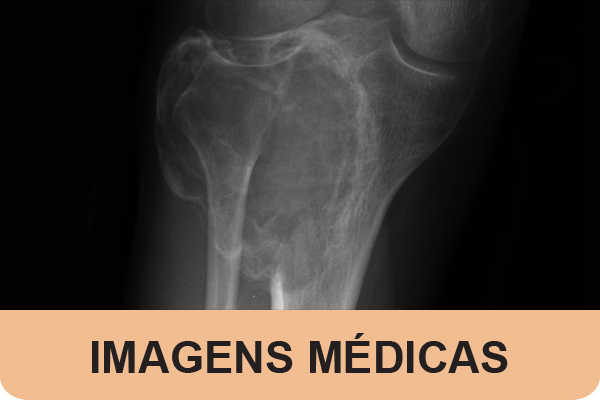

Aneurysmal bone cysts are vascular benign fibroblastic lesions usually found in bone that are locally destructive, with a greater incidenc...